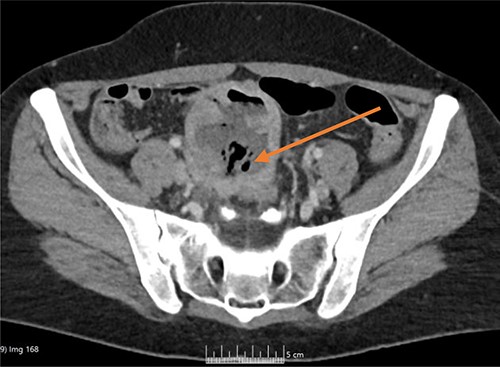

Once admitted to the haematology department, she was examined and was found to have a soft, non-tender abdomen with no signs of peritonism, and all her other systemic examinations were normal. Given the vague abdominal symptoms and blood profile, she was subjected to a CT scan of her chest, abdomen and pelvis (CT CAP). The scan reported a lower abdominal/pelvic thick-walled fluid and gas-filled structure that measured 5 × 7 × 6 cm lying adjacent to the urinary bladder with a likely fistulous tract to the overlying loops of bowel. A small amount of free fluid and non-specific stranding of fat was seen in the pelvis. No pulmonary or metastatic nodules were seen (Figs 1 and 2).

CT coronal image, with arrow showing the midline lower abdominal/pelvic thick walled fluid and gas-filled structure that measured 5 × 7 × 6 cm.